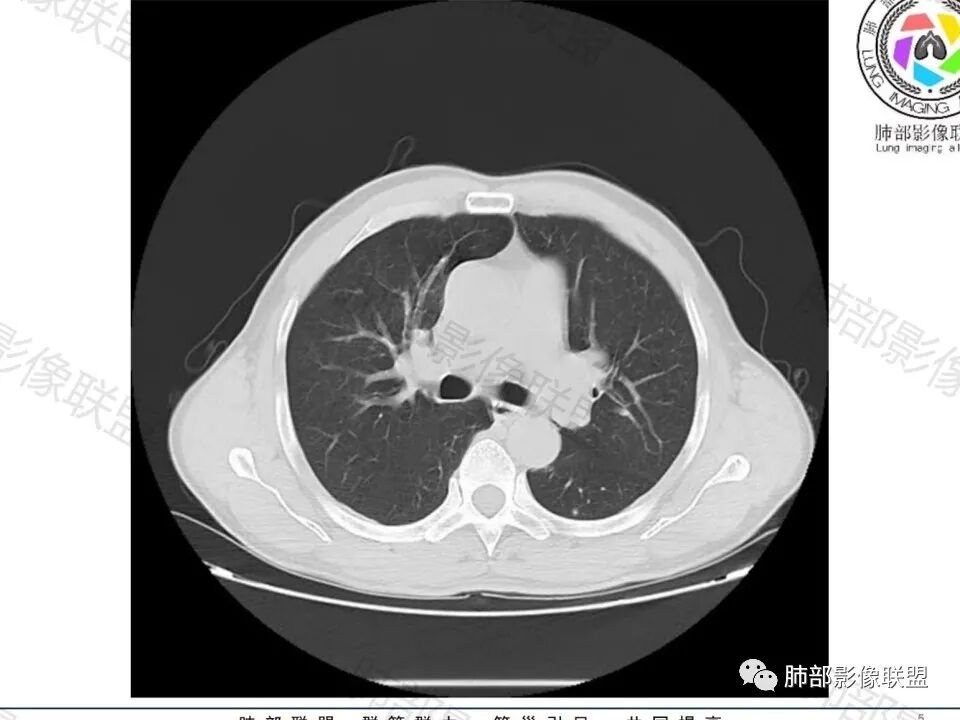

老年男性,左肺下叶背段胸膜下孤立结节,整体圆顿,周围有晕,晕中毛刺,似乎支持隐球,但边缘有一囊腔,恶性不能除外!等答案!

左肺下叶胸膜下类圆形结节,无分叶,无胸膜牵拉,周围有晕,血管支气管进入,考虑隐球菌

左下肺、右中肺均有结节,左下肺病灶比较鼓,边缘有晕,血管弯,持续性强化,考虑腺癌可能,鉴别两处病灶如果一元论,肉芽肿炎 (隐球)

老年男性,CT左肺下叶胸膜下类圆形结节,边缘光滑,无分叶,可见毛刺,相邻胸膜多条牵拉,局部胸膜增厚,(多见炎性病变),病灶周围可见模糊晕征,血管支气管进入,考虑隐球菌,现实中万万不能排除肺癌。

图做的真漂亮!老年男性,双肺多发结节,最大者位于左肺下叶胸膜下,周围有晕,晕中毛刺,边缘有一囊腔,胸膜牵拉,持续强化,考虑隐球,鉴别腺癌。

左肺下叶胸膜下类圆形结节,边缘光滑,周围有晕,晕中有毛刺,周围可见小卫星灶,相邻胸膜增厚,血管进入,右肺中叶可见小结节影,考虑炎性肉芽肿,隐球菌。鉴别腺癌。

老年男性,左肺下叶背段胸膜下结节,边缘毛刺,血管进入,斜裂有牵拉,局部胸膜糊墙,周围有晕,但有一囊腔,首先考虑腺癌,但是右肺中叶及左肺下叶还有其他结节,鉴别隐球菌

老年男性,无症状,肺气肿背景

这个囊可靠吗?

这应该是附近的肺气肿

多发类似结节

1、炎性结节,多发,类似,晕,隐球菌?

2、恶性:多发:转移瘤?肺癌并多发转移瘤?